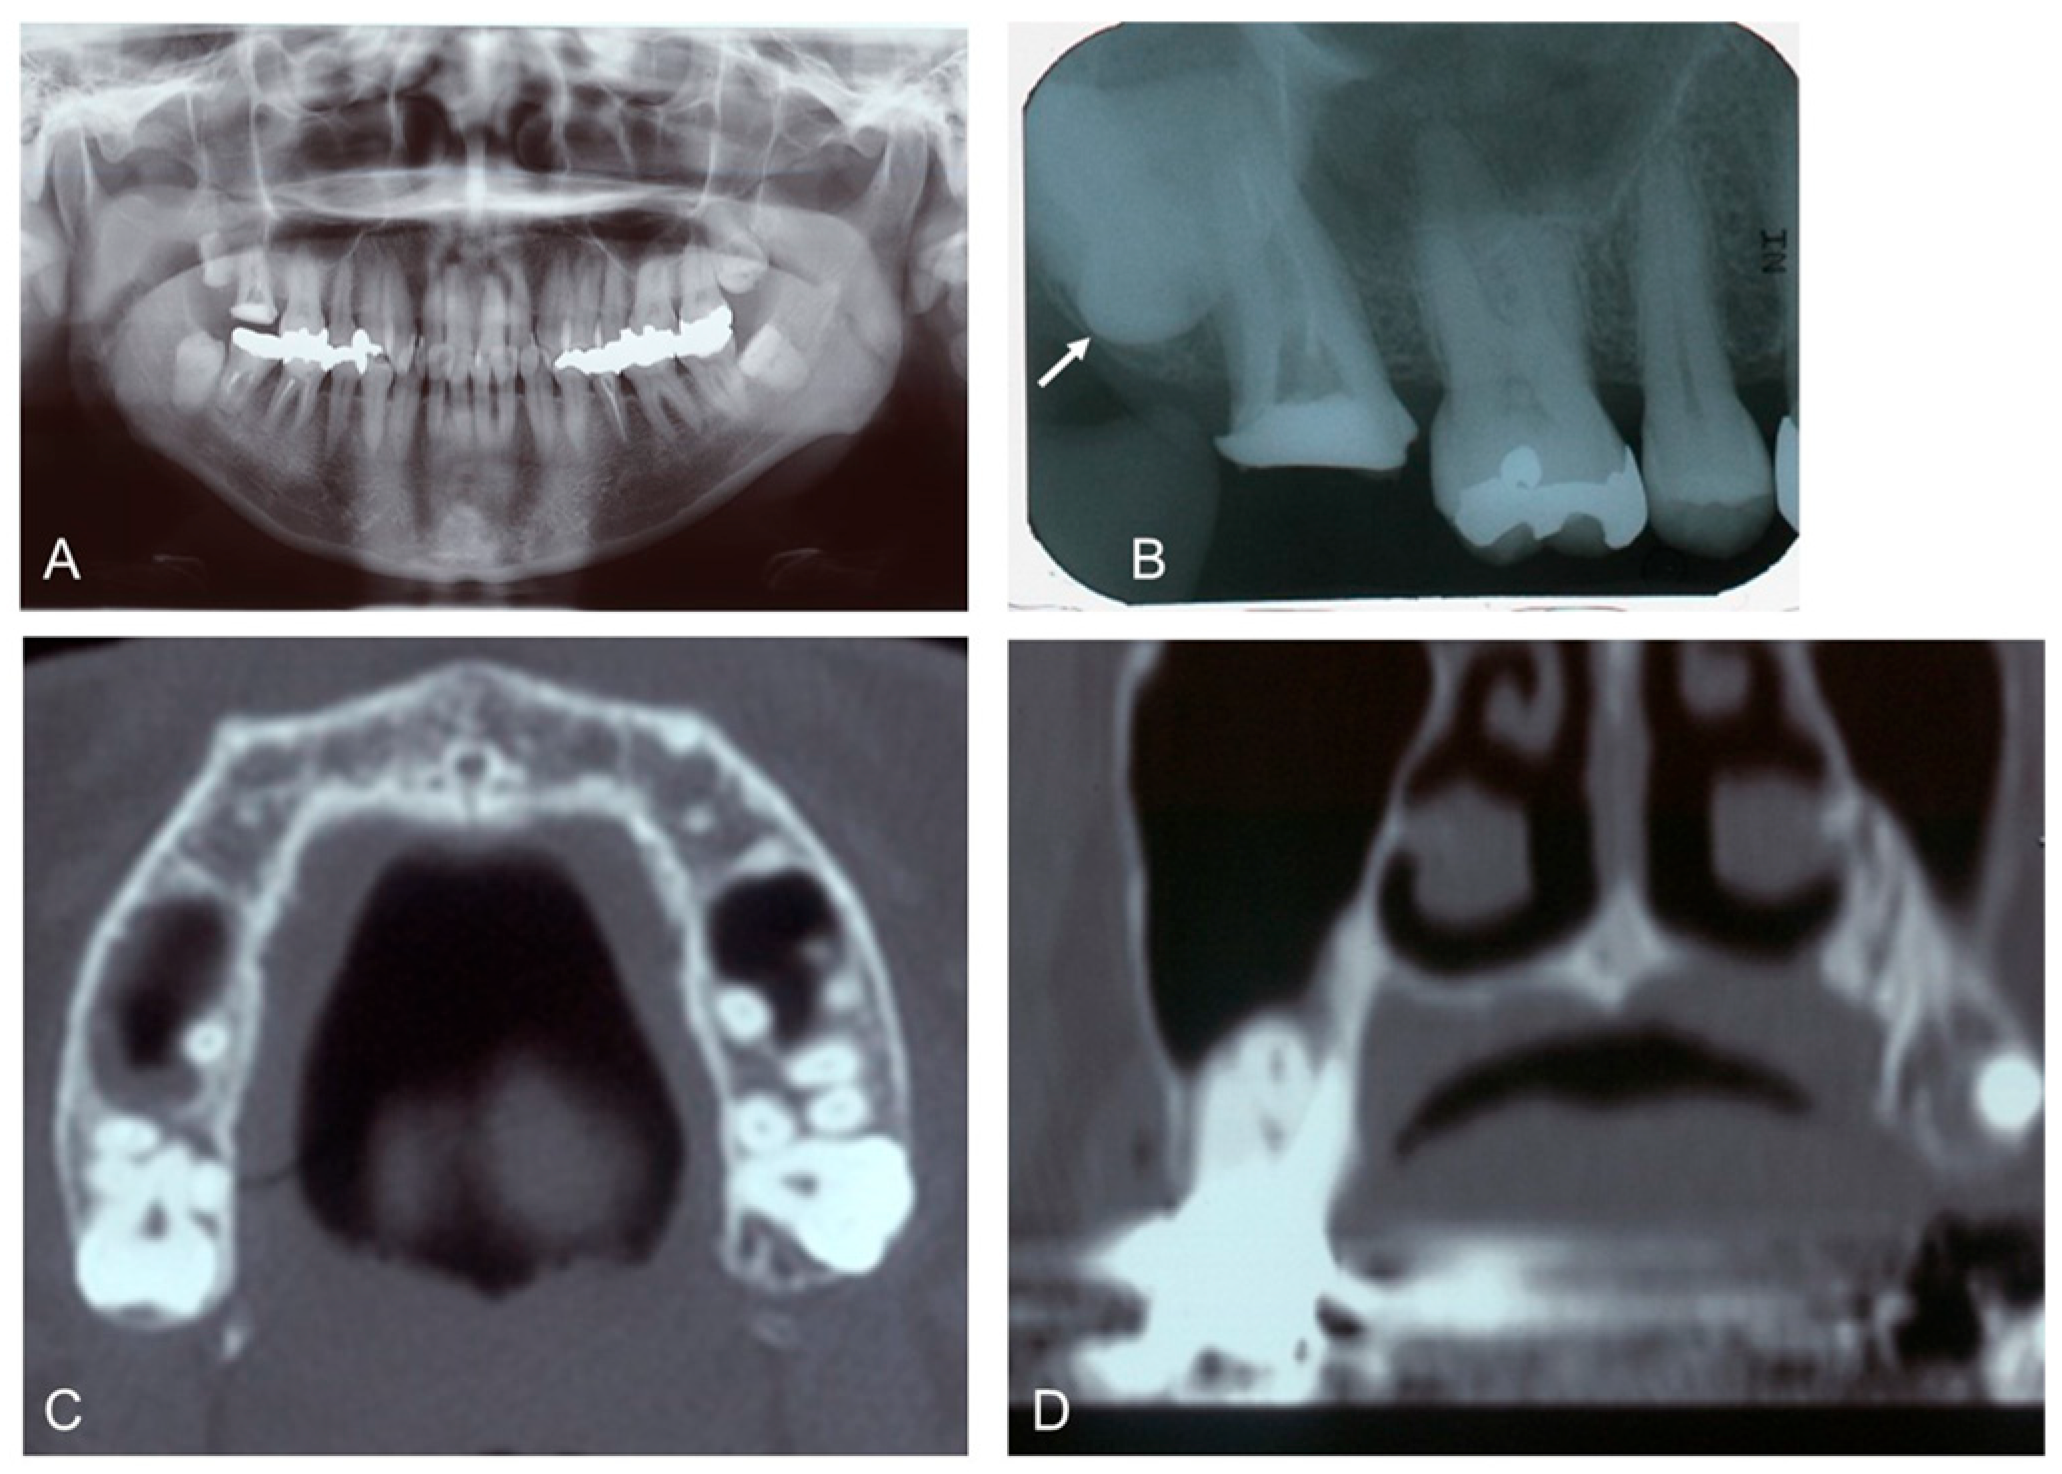

A 46-year-old female revealed a fistula at the apex of the palatal root of the upper right second molar (Tooth #2). She had a history of non-tuberculous mycobacteriosis, Hashimoto’s thyroiditis, and submucosal tumor of the large intestine. Clinical examination required the extraction of the upper right third molar (Tooth #1) and the palatal root of Tooth #1. Radiographic examination showed that the wisdom tooth (Tooth #1) was horizontally impacted in the maxilla and had the apex of a single root placed between the buccal and palatal roots of Tooth #2 (Figure 1).

Figure 1. Initial X-ray images of the 46-year-old female patient. (A): Panoramic image. Note: impacted wisdom teeth (#1, 16, 17, 32). (B): Dental image (#1, 2, 3, 4). Arrow indicates horizontally impacted tooth (#1). (C): CT (axial image). (D): CT (coronal image) showing root apex of upper right third molar (#1) placed between buccal and palatal roots of upper right second molar (#2).